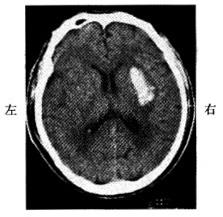

问题 男,52岁。清晨锻炼时觉头痛,左侧肢体麻木和乏力。有高血压史。半天后到急诊。查体:嗜睡,右侧肢体肌力3级,腱反射高于左侧,右侧Babinski征阳性。脑CT见图示:

可能诊断为

选项 A:脑血栓形成 B:高血压性脑出血 C:短暂性脑缺血发作 D:脑栓塞 E:脑转移癌

答案 B

解析 本题考查目的是综合临床资料,CT图像作出脑血管病的诊断。本病例为急性起病的脑血管疾病。脑血管病分为缺血性卒中和出血性卒中。脑血栓形成、短暂脑缺血发作、脑栓塞均为缺血性卒中范畴。高血压性脑出血为出血性卒中。根据脑出血性卒中和脑缺血性卒中的鉴别诊断表。可以得出B。高血压性脑出血为正确答案。脑转移癌起病较慢,而且CT的病灶周围有大片水肿,为迷惑答案。两者鉴别要点如下: